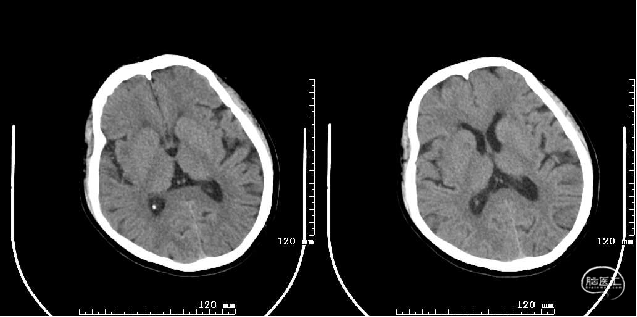

头颅MRI+DWI+MRA:右侧额颞叶及侧脑室旁急性脑梗塞,右侧大脑中动脉闭塞?右侧颈内动脉破裂孔段狭窄?

术后第二天复查头颅MRI